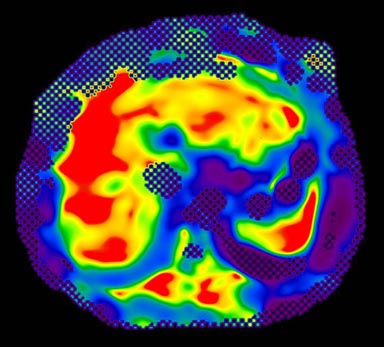

MR-Touch acquisition generates the following image types: magnitude, phase maps, wave maps, and an attenuation map. Six relative stiffness images are reconstructed for each slice location. The relative stiffness images are reconstructed in color and grey scale, and in masked and un-masked versions. Mask portion is depicted as a checkerboard pattern on the image. It is created to identify regions that should not be included in ROI measurements.

Figure 7. Color Elastogram, no mask, scale 0-20K

Figure 8. Color Elastogram, with mask, scale 0-20K